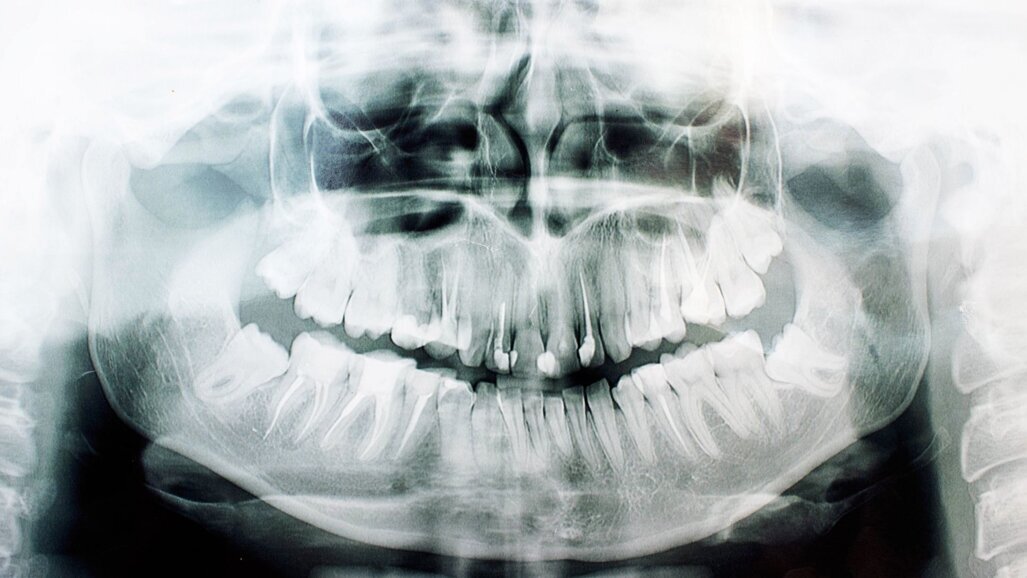

Demirjians ontwikkelingsstadia werden gescoord met behulp van panoramische röntgenfoto’s en referentiedatasets om het ontwikkelingsstadium van een verstandskies te classificeren en de chronologische leeftijd te schatten. Met name stadia G en H zijn in dit opzicht van belang. In stadium G zijn de wortelpunten nog open, terwijl ze in stadium H gesloten zijn, waarmee de vorming van de tand is afgerond. De tandvorming wordt beïnvloed door factoren zoals geslacht, etniciteit en genetica. Omgevingsstress heeft meestal een minimaal effect, maar voeding, episoden met hoge koorts en bepaalde medicijnen kunnen de ontwikkeling van de tand wel beïnvloeden.

Vanuit technisch oogpunt is met name beeldkwaliteit cruciaal voor het bepalen van de leeftijd op basis van het ontwikkelingsstadium van de verstandskiezen, maar op röntgenfoto´s kan sprake zijn van onopgemerkte vervormingen die de betrouwbaarheid beïnvloeden. Geavanceerde methoden zoals machine learning zouden het schatten van de leeftijd in de toekomst kunnen verbeteren.